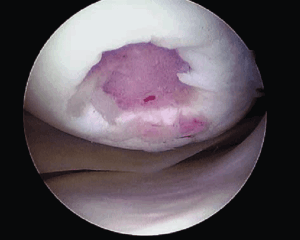

• Травмы циклопа:

о Очаговая фиброзно-синовиальная ткань в передней межмыщелковой вырезке

о На артроскопии определяется «голова» с центральной областью нарушения пигментации; отсюда вытекает название травма циклопа